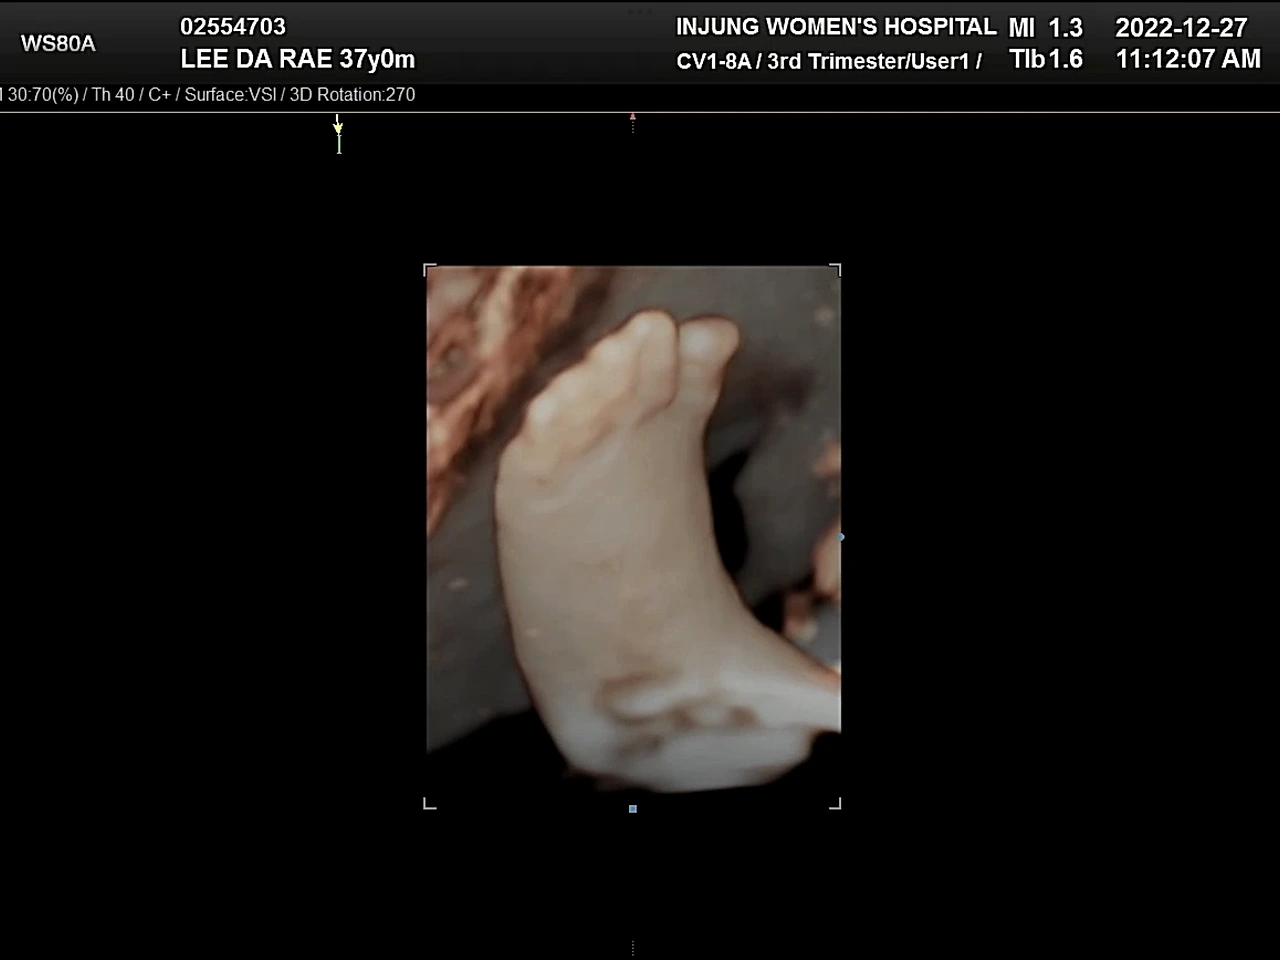

귀여운 손발

28주 즈음, TV에서 다섯 쌍둥이를 낳은 부부를 봤다. 28주에 낳았다는데, 출산당시 아이들의 모습을 보니 정말 사람의 모습을 하고 있어서 신기했다. 포도의 모습은 선명하진 않지만 초음파로도 많이 봤고, 이미 입체초음파도 본 상태인데 그게 왜 새삼 신기했는지. 배를 쓰다듬으며 얼른 보고 싶다고 건강하게 만나자고 속삭여주었다.